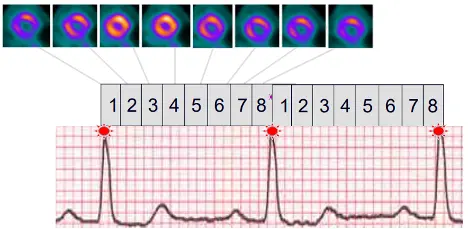

tl;dr: We collect transmission and perfusion images and superimpose them on one another. The CT and perfusion contours of the heart should be properly aligned (co-registration).

- Scout image to localize the heart

- Transmission scans – most commonly done with low-dose CT AC

- Emission scans

- Patient is